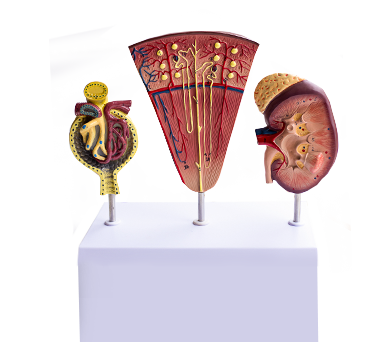

Практикующий врач-терапевт, нефролог, кмн.

Я - практикующий врач-терапевт, врач-нефролог, кандидат медицинских наук, доцент кафедры.

Мои услуги

1. УЗИ почек и мочевыделительных путей